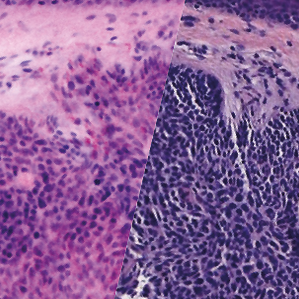

Basal cell carcinoma; imaged with the VivaScope 2500 (left) and after H&E staining (right)

Images courtesy of Dr Javiera Pérez-Anker.